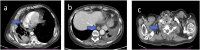

Background: Malignant pleural mesothelioma is the most common primary tumor of the pleura. The unique growth pattern of malignant pleural mesothelioma makes it difficult to apply the Response Evaluation Criteria for Solid Tumors (RECIST). Hence the need to use modified RECIST (mRECIST) criteria, as they better fit the unique growth pattern of malignant pleural mesothelioma. The thickness of the tumor perpendicular to the chest wall or mediastinum is measured at 2 points at 3 separate levels at least 1 cm apart on chest CT scans, and summed to obtain a one-dimensional pleural measurement. The same criterion has also been used to assess response to treatment. RECIST 1.1 represents a further update, taking into account new concepts such as revised minimum dimensions for lymph nodes and an approach to lesions that become non-measurable. Based on experience and published literature, the hypothesis of merging the 2 above-mentioned criteria in mRECIST 1.1 for mesothelioma and the use of iRECIST for the application to immune-based therapies (iRECIST) was considered. Purpose: Support the importance of studying pleural mesothelioma in a reliable and reproducible way, through a scrupulous methodology, applying the mRECIST1.1 and iRECIST criteria. Conclusions: Adoption of a standardized study metodology can make the study of PM reproducible and correct.